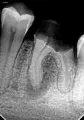

6-ка снизу слева начала беспокоить примерно полгода назад, появились ноющие болевые ощущения. Когда я обратилась к врачу, был сделан снимок. Врач сказал, что необходимо его депульпировать, так как обширная пломба очень близко располагается к нерву. Но вопрос стоял в том, что у меня установлены брекеты и не получится убрать полностью старую пломбу. Было принято решение сделать ванночки с содой, а если не пройдет, то вскрывать и удалять нерв. В итоге зуб прошел на второй день. Но через какое то время появился свищ. Зуб в данный момент не болит, при простукивании на осмотре нет никаких неприятных ощущений. Врач в свищ ввела гуттаперчу и сделала снимок, чтоб посмотреть, откуда свищ выходит. На снимке видно, что к корням.

Есть ли хоть какие-то шансы спасти данный зуб?

В периапикальных тканях зуба имеется обширное воспаление. Необходимо снять брекет и пролечить зуб, в противном случае деструктивный процесс будет прогрессировать.